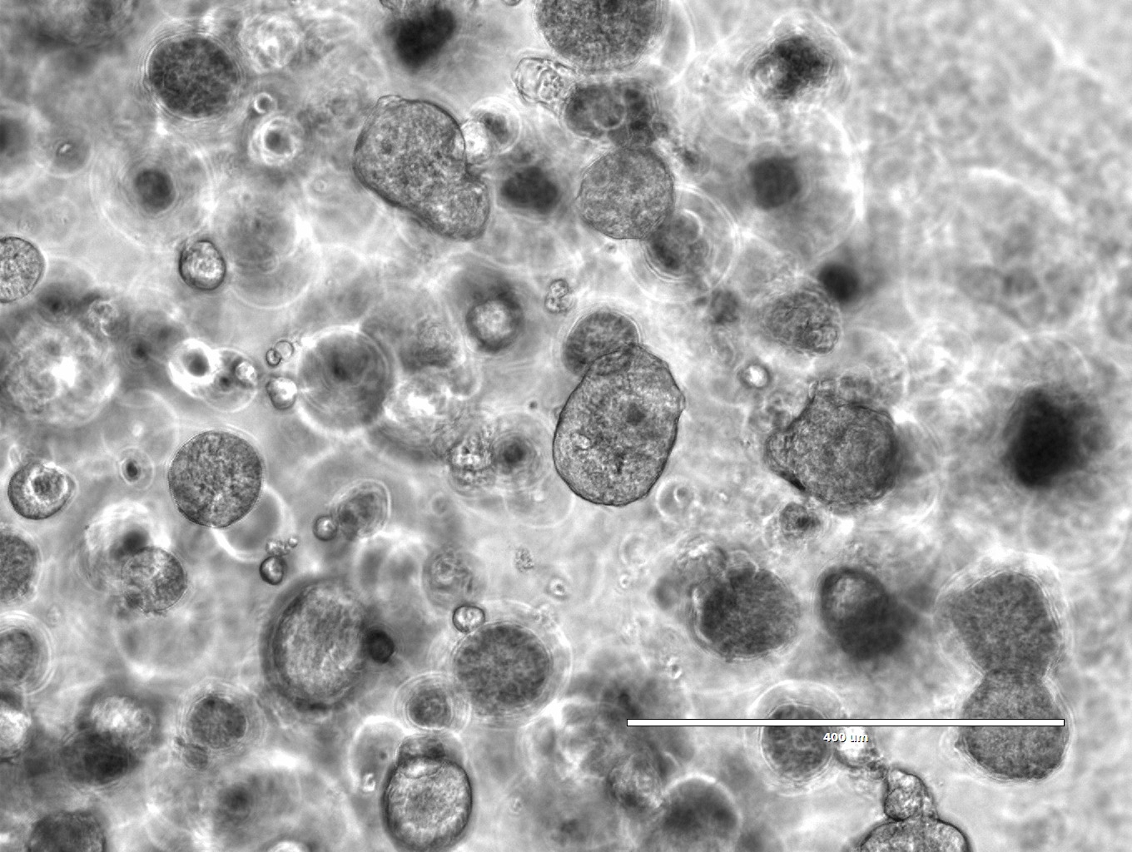

• 来源于乳腺癌病人的三维类器官形态观察